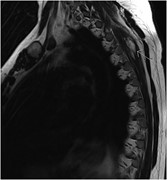

Primary mediastinal dedifferentiated liposarcoma resected by lateral thoracotomy with video-assisted thoracoscopic surgery

Kazutoshi Hamanaka and others

Journal of Surgical Case Reports, Volume 2016, Issue 1, January 2016, rjv163, https://doi.org/10.1093/jscr/rjv163